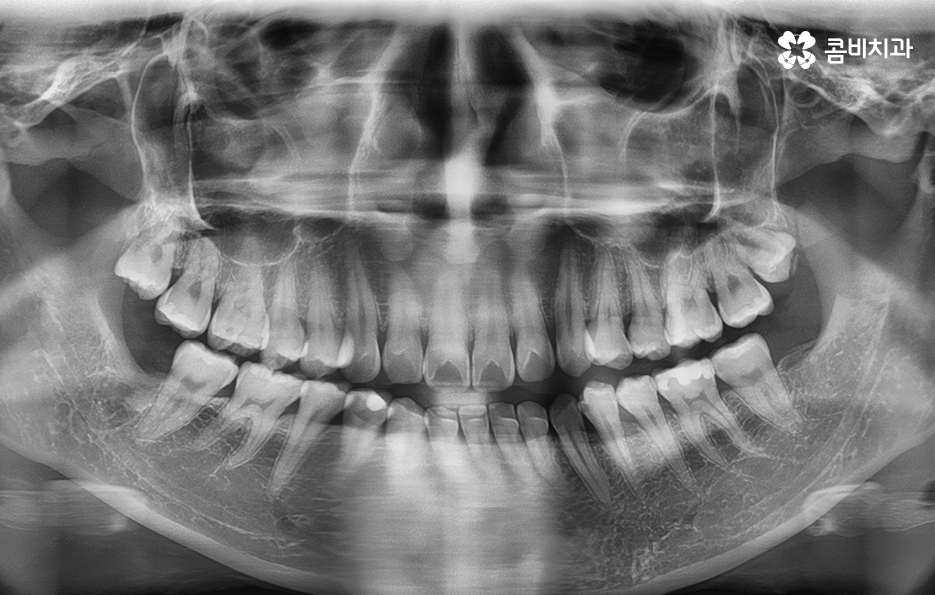

위 엑스레이 사진을 보시면 파란 원을 그린 부분이

발치를 한 부위이며 교정 기간이 경과함에 따라서

이 공간이 점점 메워지게 되고

가지런한 치열은 물론 돌출입도 개선됩니다.